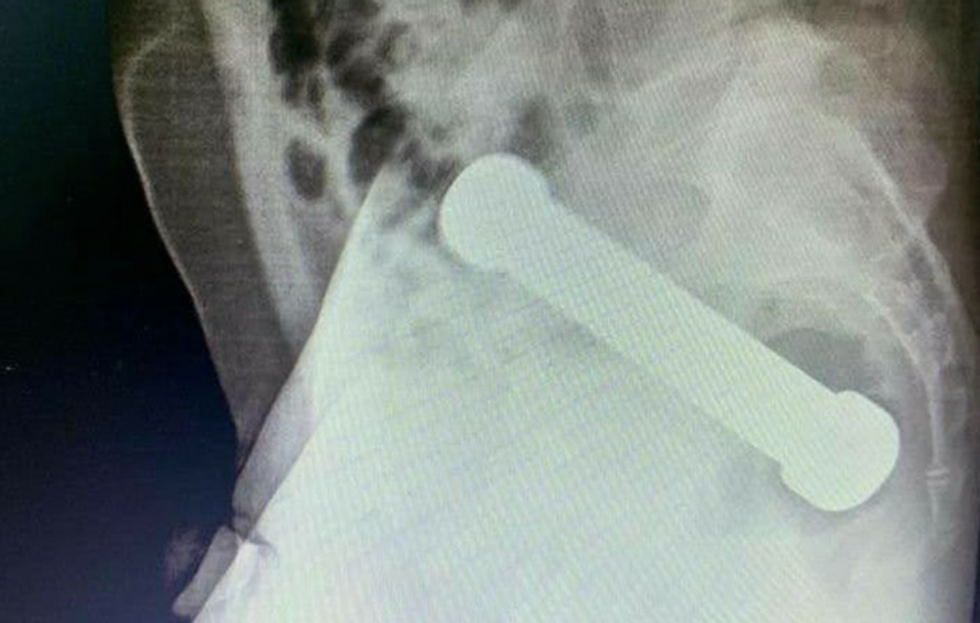

Doctors requested an X-ray of his abdomen after an initial examination that struggled to find the cause - and the man was also reportedly hesitant to unveil what he surely knew was causing him discomfort.

The X-rays spotted a metallic 2kg dumbbell which was about 20cm long and lodged in the area where the colon meets the rectum.